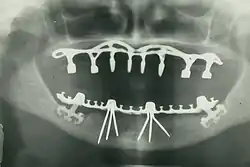

- Oral and maxillofacial radiology – the study and radiologic interpretation of oral and maxillofacial diseases.

- Oral and maxillofacial surgery (also called oral surgery) – extractions, implants, and surgery of the jaws, mouth and face.[nb 2]